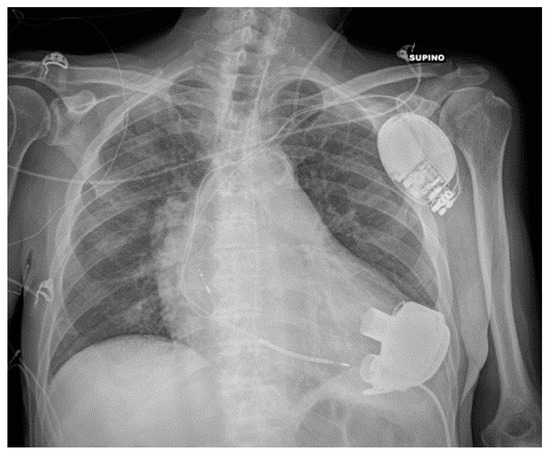

5.2. Pacemaker (PM) and Automatic Implantable Cardioverter-Defibrillator (AICD)

| PM and AICD | Leads misposition/breakage |

| Twiddler’s syndrome | |